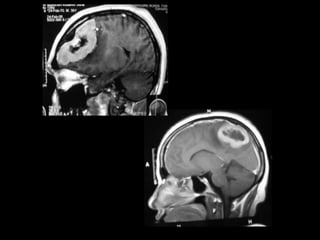

MRI

• Extra-axial dural based lesion- a mass is said to be

dural based when the greatest diameter occurs at

the margin of the tumor that abuts against the

dural surface

• Extra-axial- interface present, dilated subarachnoid

space, buckling of white matter

• Displacement, encasement, narrowing & occlusion

of surrounding vessels better visualized

• T1 – 60% are isointense,

30% mildly hypointense

to gray matter

MRI-T2

• On proton density & T2

isointense(50%), mild to

moderate

hyperintensity(40%)

• Hyperintensity S/O

higher water content-

probably

meningothelial,vascular,

aggressive,microcystic

Contrast MRI

• Homogenous contrast

enhancement-intense

and uniform

• Dural tails-histologically

has connective tissue .

Vascular tissue

,meningioma cell nests